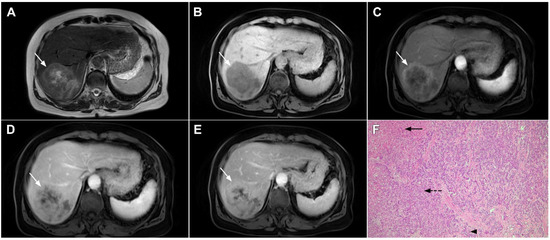

Target sign, consisting of diffusion restriction at the periphery of the lesion and low signal intensity in its central parts on high-b-value diffusion weighted imaging (DWI), could be considered to be a pathognomonic finding in mICC [16,17]. It can be attributed to the loose central fibrotic stroma with accompanying edema that is responsible for low signal intensity in DWI, while the periphery of the lesion is composed of densely packed viable tumor cells that cause diffusion restriction and dark rings on the apparent diffusion coefficient (ADC) map (Figure 3) [16].

Figure 3.

Mass-forming intrahepatic cholangiocarcinoma in the left liver lobe of a 76-year-old man. Axial T2-weighted FS image shows lobulated hetrogeneously hyperintense hepatic tumor (arrow) with perilesional biliary dilatation (A). Axial diffusion-weighted image (b = 800 s/mm2) shows target-like appearance (arrow) of the lesion that consists of a central darker area and a peripheral hyperintense area (B). Corresponding ADC map is shown on (C).

If hepatocyte-selective contrast media are used, mICC presents typically as hypointense lesions on the hepatobiliary phase due to the lack of functional hepatocytes with a sharp margin between the tumor and the background liver parenchyma [7]. Thus, tumor size as well as the presence of perilesional satellite nodules, could be more precisely evaluated in the hepatobiliary phase in comparison to the MRI with conventional extracellular contrast [18,19]. Additionally, the “cloud sign”, seen as a relatively high cloud-like signal intensity in the central part of the lesion surrounded by a hypointense peripheral rim, is considered characteristic of mICC (Figure 4) [19]. The appearance of mICC in the hepatobiliary phase may be used as a prognostic factor since it correlates well with the content of intralesional fibrous stroma [20]. Namely, if cloud sign is seen it indicates a large amount of fibrous stroma in the central parts of the tumor, which is frequently associated with poor prognosis [20]. Additional imaging features, which are shown to be prognostic factors and can be assessed in the hepatobiliary phase, include capsule penetration and hepatic vein obstruction, as was demonstrated in the study by Kim S et al. [21].

Figure 4.

Mass-forming intrahepatic cholangiocarcinoma in a 68-year-old woman. Axial T1-weighted image after gadoxetic acid administration obtained in arterial phase (A) shows peripherally enhancing lesion (arrow). Portal venous phase in the same patient (B) shows progressive centripetal enhancement of the lesion (arrow) with cloud-like appearance in the hepatobiliary phase (C) consisting of an area of central enhancement and a thin, peripheral, hypointense rim.